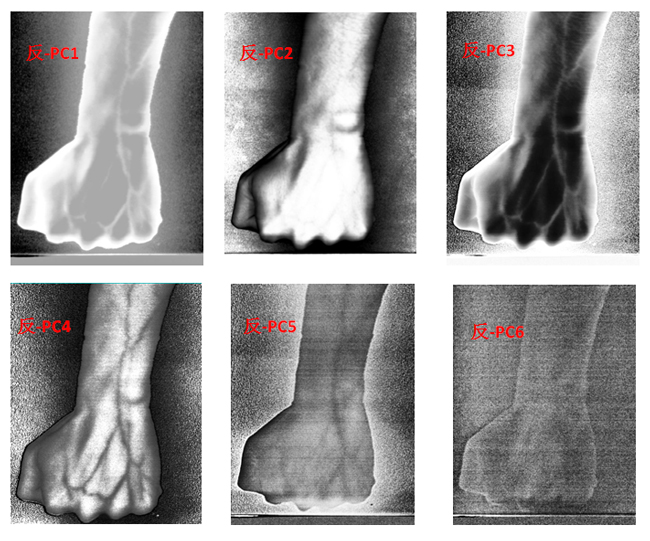

為了客觀地識別手臂上的靜脈,對經(jīng)預處理后的高光譜數(shù)據(jù)進行主成分分析(Principal Component Analysis, PCA),去除波段之間的多余信息、將多波段的圖像信息壓縮到比原波段更有效的少數(shù)幾個轉換波段下。圖9為手臂正反面經(jīng)PCA變換后的前6個主成分。

圖9 手臂正反兩面PCA處理后的前6個主成分

為了更客觀真實地識別出手臂靜脈,根據(jù)波段組合的特點,對PCA前六個主成分組合成各種假彩色圖像,如圖10為手臂正面的假彩色合成圖像,圖11為手臂反面的假彩色合成圖像。與灰度圖相比,假彩色合成更能直觀地識別出手臂靜脈。

圖11 手臂反面PCA假彩色合成圖像